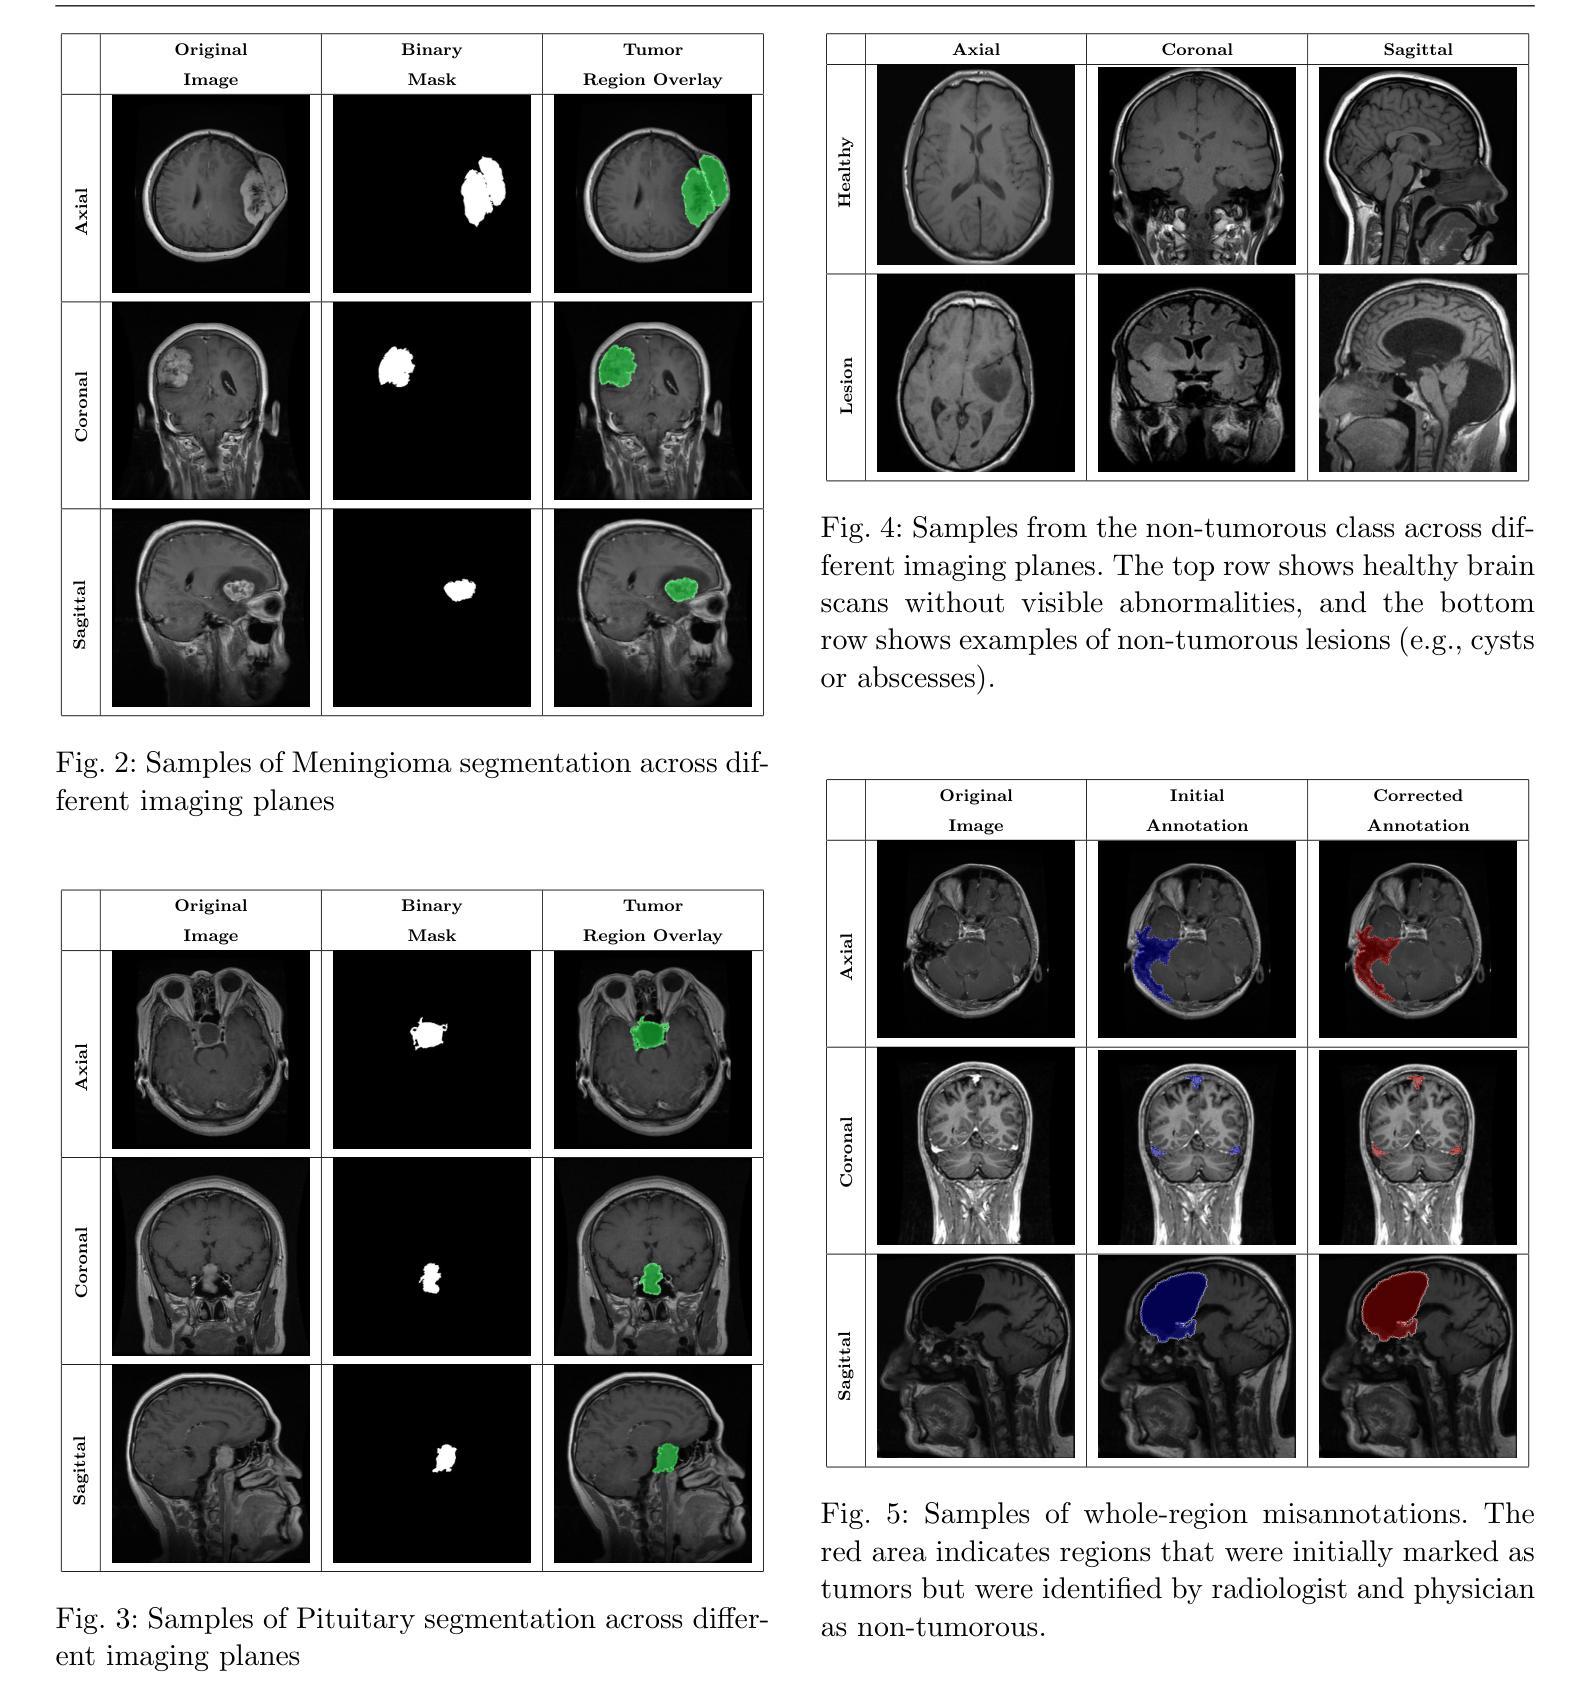

Accurate segmentation and classification of brain tumors from Magnetic Resonance Imaging (MRI) remain key challenges in medical image analysis, primarily due to the lack of high-quality, balanced, and diverse datasets with expert annotations. In this work, we address this gap by introducing BRISC, a dataset designed for brain tumor segmentation and classification tasks, featuring high-resolution segmentation masks. The dataset comprises 6,000 contrast-enhanced T1-weighted MRI scans, which were collated from multiple public datasets that lacked segmentation labels. Our primary contribution is the subsequent expert annotation of these images, performed by certified radiologists and physicians. It includes three major tumor types, namely glioma, meningioma, and pituitary, as well as non-tumorous cases. Each sample includes high-resolution labels and is categorized across axial, sagittal, and coronal imaging planes to facilitate robust model development and cross-view generalization. To demonstrate the utility of the dataset, we provide benchmark results for both tasks using standard deep learning models. The BRISC dataset is made publicly available. datasetlink: Kaggle (https://www.kaggle.com/datasets/briscdataset/brisc2025/), Figshare (https://doi.org/10.6084/m9.figshare.30533120), Zenodo (https://doi.org/10.5281/zenodo.17524350)

从磁共振成像(MRI)对脑肿瘤进行精确分割和分类,在医学图像分析领域仍是关键挑战,这主要是因为缺乏带有专家注释的高质量、均衡和多样化的数据集。在这项工作中,我们通过引入BRISC数据集来解决这一差距,该数据集专为脑肿瘤分割和分类任务设计,具有高质量分辨率分割掩膜。该数据集包含6000张增强型T1加权MRI扫描图像,这些图像是从多个缺少分割标签的公开数据集中整理的。我们的主要贡献是对这些图像进行了随后的专家注释,这些注释由认证过的放射学家和医生完成。它包含三种主要的肿瘤类型,即胶质瘤、脑膜瘤和垂体瘤,以及非肿瘤病例。每个样本都包含高分辨率的标签,并按轴向、矢状和冠状成像平面进行分类,以促进稳健的模型开发和跨视图推广。为了证明数据集的有效性,我们使用标准深度学习模型为两个任务提供了基准测试结果。BRISC数据集已公开发布。数据集链接:Kaggle(https://www.kaggle.com/datasets/briscdataset/brisc2025/)、Figshare(https://doi.org/10.6084/m9.figshare.30533120)、Zenodo(https://doi.org/10.5281/zenodo.17524350)

Summary

本文介绍了一个专为脑肿瘤分割和分类任务设计的数据集BRISC,包含了经过专家标注的高分辨率分割掩膜。该数据集由6000个对比增强的T1加权MRI扫描组成,涵盖了三种主要肿瘤类型(胶质瘤、脑膜瘤和垂体瘤)以及非肿瘤病例。每个样本都按轴向、矢状面和冠状面进行分类,以促进稳健的模型开发和跨视图泛化。为展示该数据集实用性,本文提供了使用标准深度学习模型的基准测试结果,并公开提供BRISC数据集。

Key Takeaways

1. BRISC数据集专为脑肿瘤分割和分类任务设计,解决了当前医学图像分析中缺乏高质量、平衡和多样化数据集的问题。

2. 数据集包含经过专家标注的高分辨率分割掩膜,有助于提高模型的准确性和泛化能力。

3. 数据集包含三种主要肿瘤类型(胶质瘤、脑膜瘤和垂体瘤)以及非肿瘤病例,为模型训练提供了丰富的数据样本。

4. 每个样本都按轴向、矢状面和冠状面进行分类,促进了模型在跨视图情境下的泛化能力。

5. 通过使用标准深度学习模型进行基准测试,证明了BRISC数据集的实用性。

6. BRISC数据集已公开提供,方便研究人员使用。